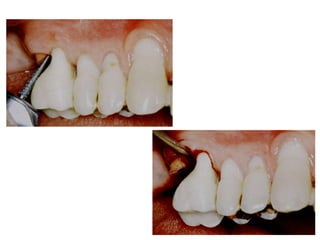

Cálculos subgengivais

Furcas classe I

PI -3mm periodontitis leve a moderada

Furcas Classe II

PI de 3mm o + (periodontitis avanzada)